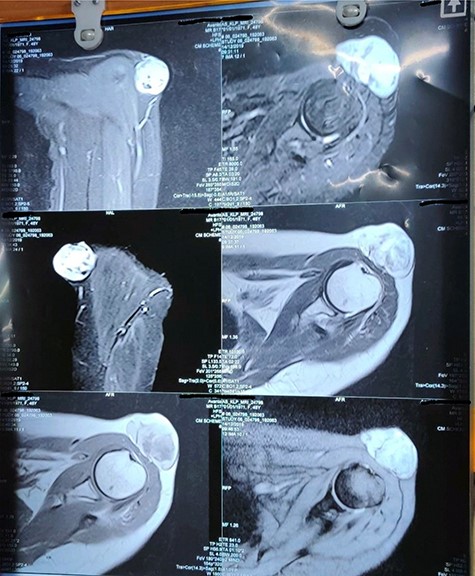

The patient was evaluated and magnetic resonance imaging of the left shoulder was done, which showed a solid cystic mass lesion with haemorrhagic areas involving superficial and deep subcutaneous plane with no intramuscular/bony involvement, with the possibility of a soft tissue sarcoma. There was no nodal involvement on radiological imaging (Fig. 2).